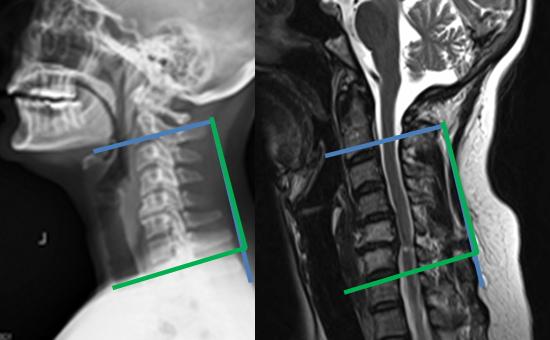

9. A 67-year-old man falls forward from standing height sustaining a hyperextension injury to his neck. He has neurological deficits present on physical examination. A radiograph, CT scan and MRI are seen in Figures A, B and C. Which of the following MOST likely characterizes his neurologic examination?"

FIGURES: A

B

C

DISCUSSION: The patient in the scenario has a central cord syndrome. The images show a relatively kyphotic spine with moderate osteophyte formation from C4 through C6. The MRI shows stenosis without cord signal change. Central cord syndrome is characterized by motor deficits more pronounced in the upper extremities than lower extremities. In addition, finger and wrist motor function is more affected than shoulder and biceps function. Sensory deficits are usually minimal.

Nowak et al reviewed central cord syndrome. It is the most common incomplete spinal cord injury, typically resulting from an extension injury. It presents as a spectrum from hand weakness to quadraparesis with sacral sparring. Early surgical treatment is still controversial.